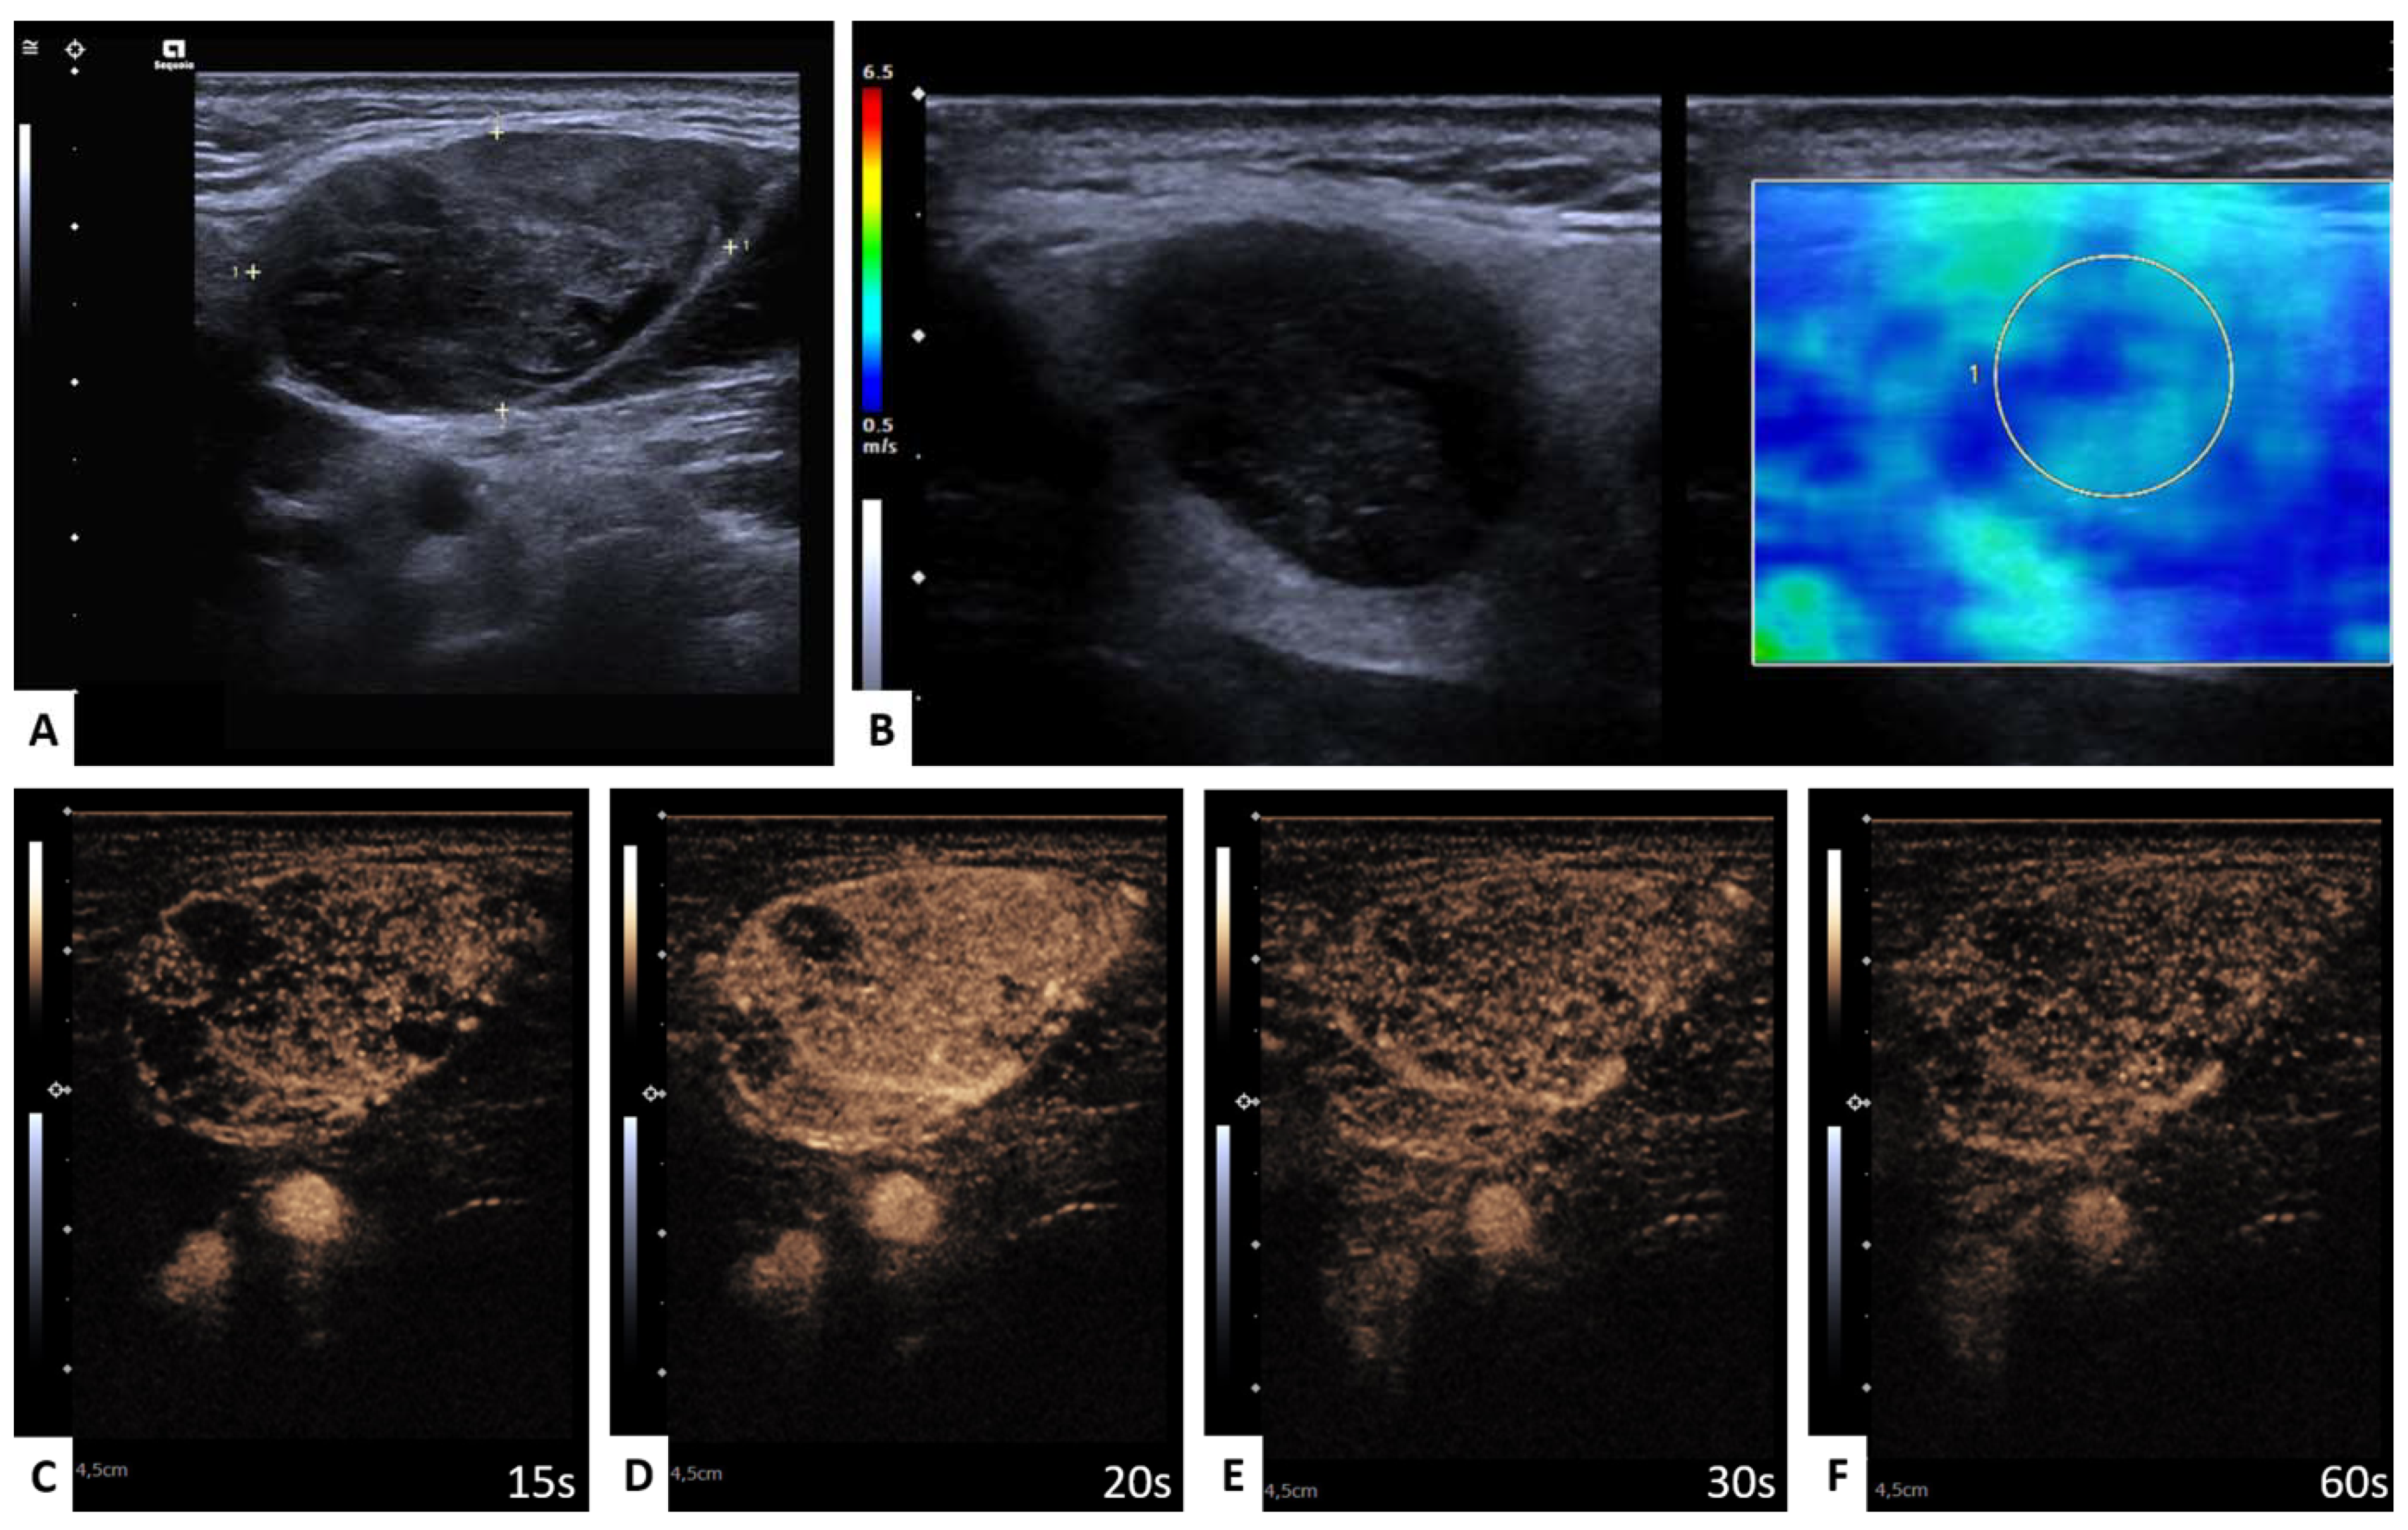

3.4.1. WT versus PA